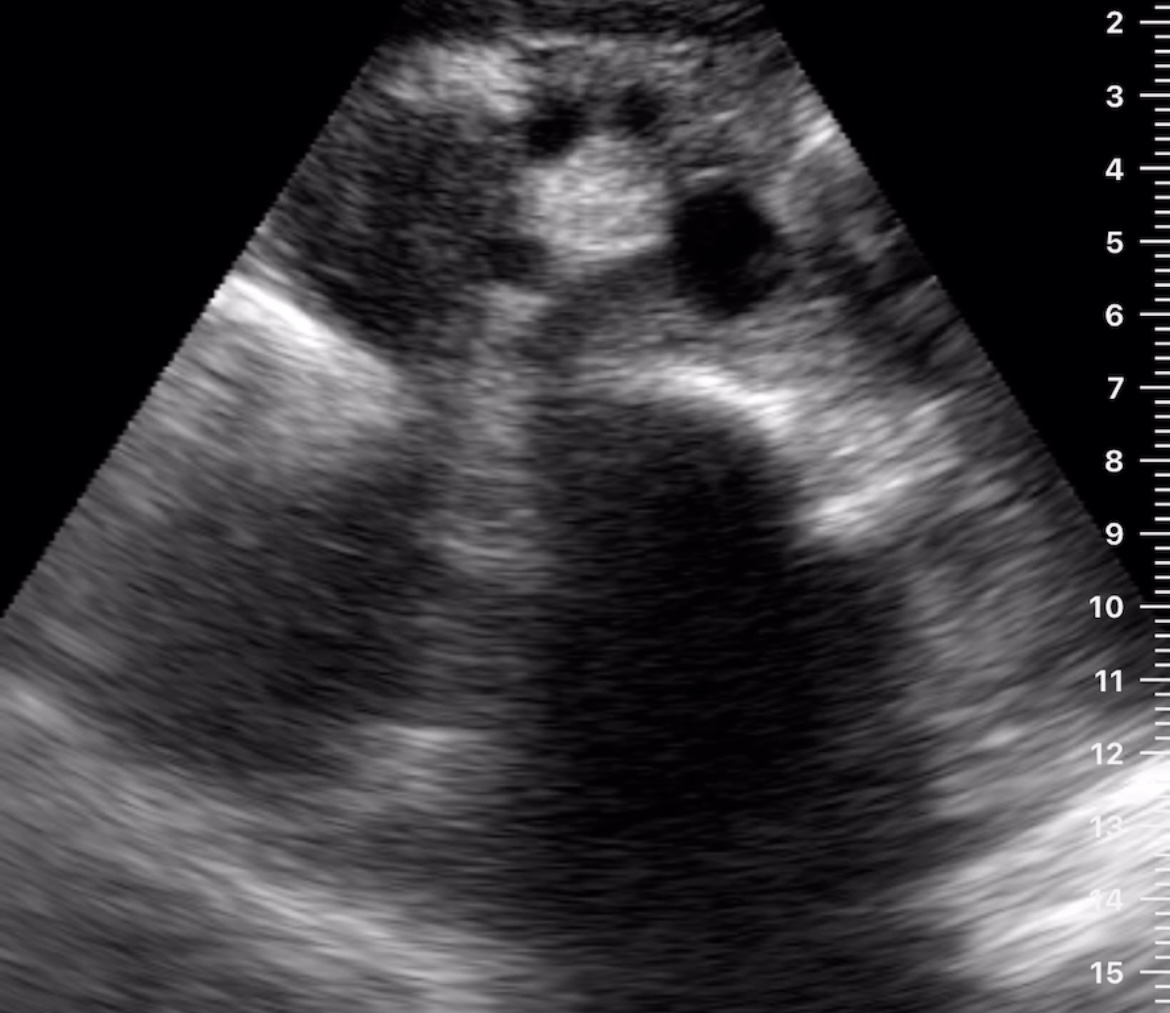

Hallazgos ecográficos

Observamos una lesión a nivel de la cabeza del páncreas, de bordes mal definidos, hipoecogénica, además de dilatación del conducto de Wirsung y dilatación de la vía biliar tanto intra como extrahepática.

Posteriormente se realizó ecoendoscopia, donde se evidenció una lesión de características malignas de 3,7 cm en la cabeza del páncreas que infiltra eje esplenoportal y contacta con AMS sin poder descartar infiltración de la misma y adenopatías de aspecto patológico. Los resultados de la biopsia se informan como adenocarcinoma de páncreas.